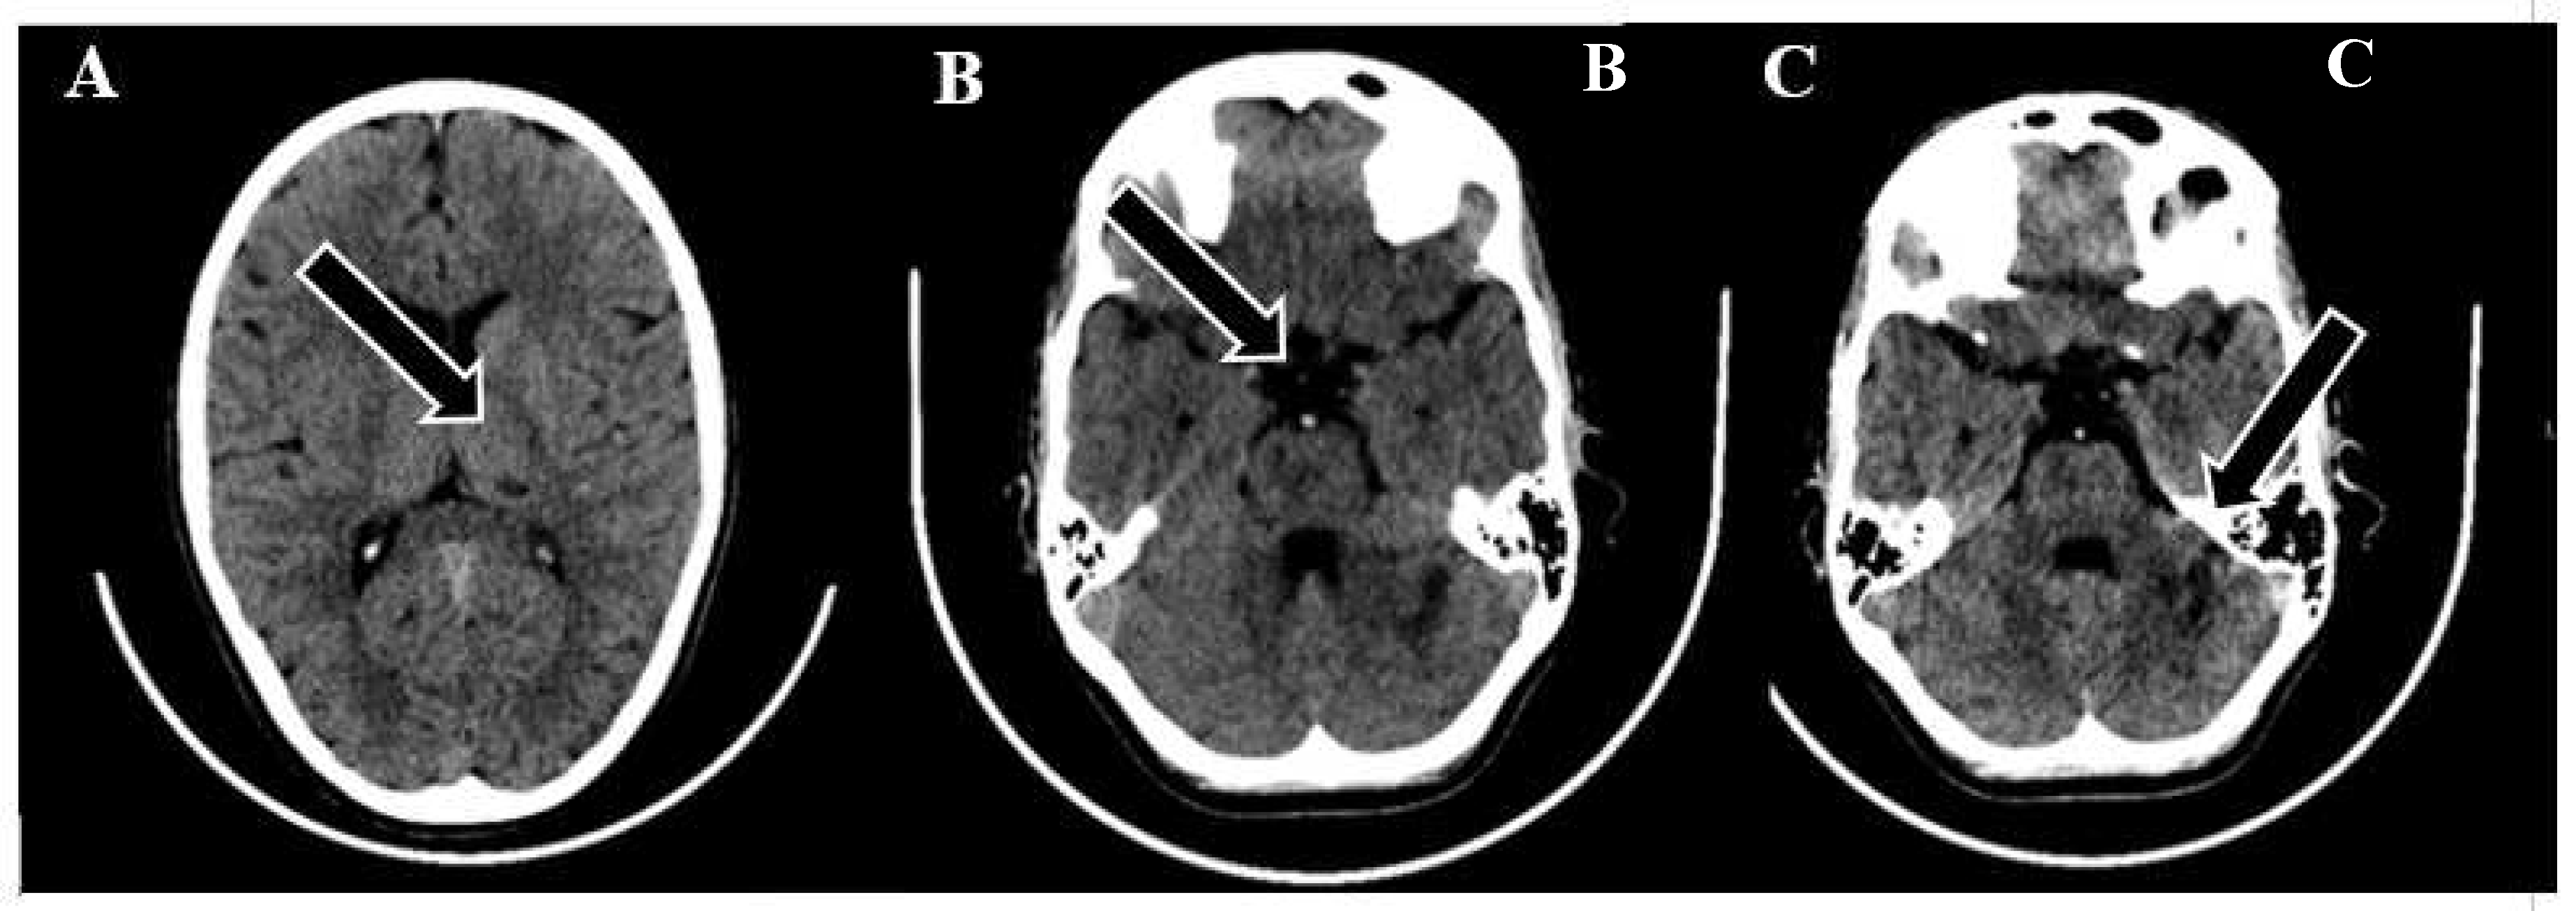

Figure 3. Neurointerventional procedure. (A, B) Initial angiogram from anterior-posterior and lateral views reveals an upper third basilar artery occlusion and no enhancement in both posterior cerebral arteries (TICI scale: 0). (C, D) After the first attempt, angiogram views show improved basilar artery enhancement, but filling defects and absent enhancement persist in both posterior cerebral arteries. (E, F) Post-thrombectomy angiograms demonstrate enhanced perfusion in the basilar artery and both posterior cerebral arteries (TICI scale: 3).

Under the administration of general anesthesia, a retrograde puncture was performed in the right common femoral artery, utilizing a 5F sheath. Subsequent to this, a left vertebral angiogram was conducted, revealing a significant blockage in the upper third of the basilar artery. This obstruction resulted in an absence of contrast in both posterior cerebral arteries, which was graded as Thrombolysis in cerebral infarction (TICI) scale score of 0, indicating minimal to no blood flow.

To restore normal blood flow to the affected areas, an aspiration catheter known as "Sofia" was carefully positioned in the distal V2 segment. Throughout the procedure, multiple left vertebral arteriograms were performed, consistently illustrating blockages in the middle segment of the basilar artery. After six meticulous attempts, a final angiogram conclusively confirmed the complete removal of the obstructions in both the basilar artery and the posterior cerebral arteries, achieving a TICI scale score of 3, indicating full and successful revascularization.